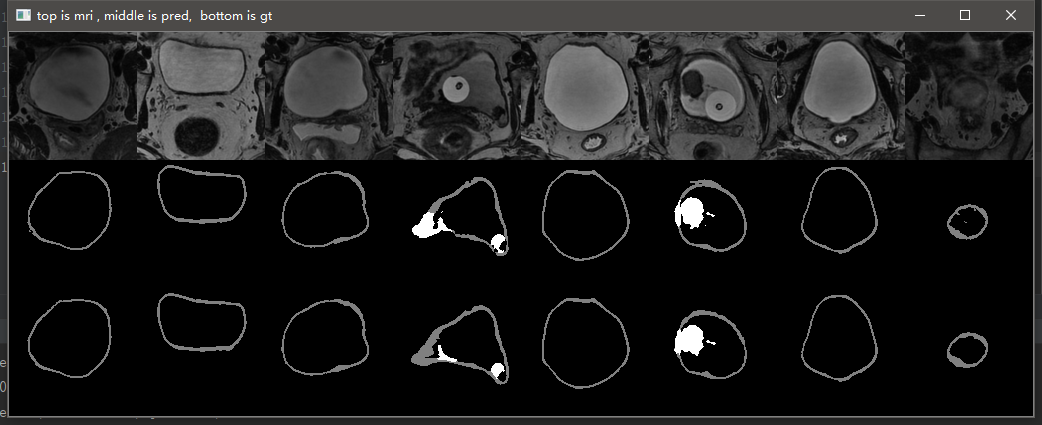

3.10 实验结果

这是笔记本跑了10个epoch的结果,仅仅是测试代码有没有问题。从结果可以看到,代码目前应该是没有问题的,后期只需调参数再训练提升效果即可。

GTX2080TI 跑120个epoch的测试效果:

Val Mean Dice = 0.9051, Val Bladder Dice = 0.9012, Val Tumor Dice = 0.9091